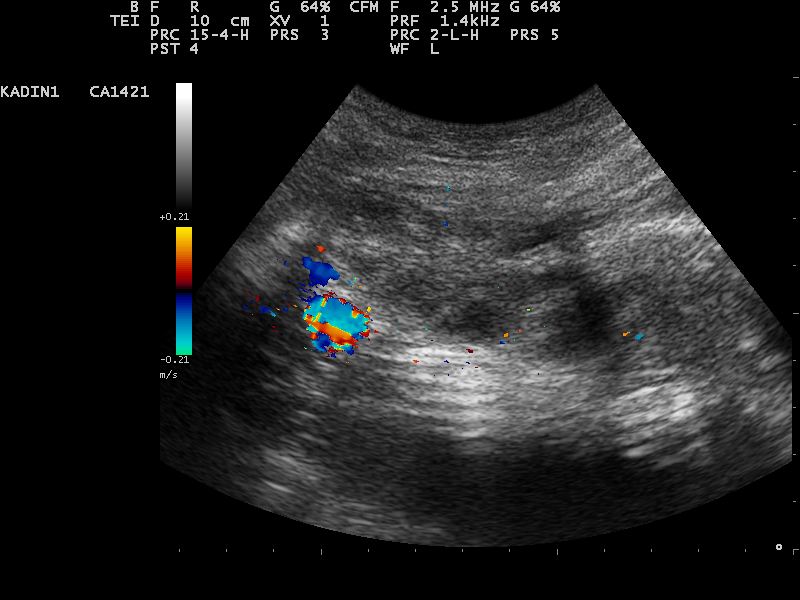

過了漫漫長夜,我再度開立轉診單,轉診單上寫著媽媽的症狀以及做過的相關檢查,高度懷疑可能是左側卵巢囊腫扭轉;出門前,我跟爸媽說,要多帶些衣物,有可能需要開刀。早上八點立刻到婦產科報到,婦產科醫師是我的老師,幫媽媽做超音波確認卵巢囊腫,並且高度懷疑卵巢扭轉(ovarian torsion)的可能性。